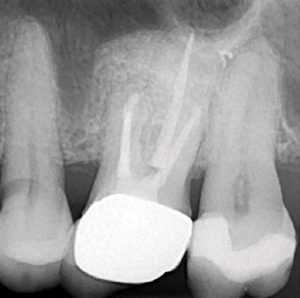

After debridement and shaping, Ca(OH)2 (Ultrocal XS) was placed in the root canal space to further enhance disinfection. Prior to obturation, drainage was noted coming from the MB2 canal; drainage was arrested and the canals root was filled with vertical condensation of warm gutta percha (VCWG) and AH-Plus sealer (Figure 3)